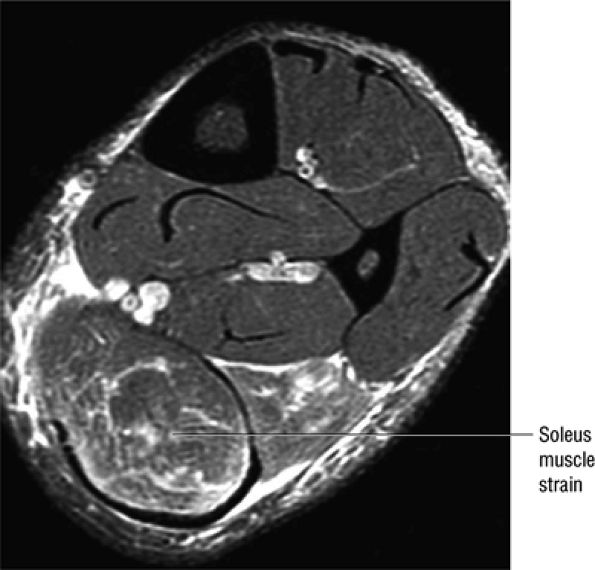

FIGURE 5.128 ● Grade 1 soleus muscle strain secondary to an Achilles rupture. Axial FS PD FSE image.

Achilles tendon rupture usually occurs 2 to 6 cm proximal to its os calcis insertion.

Axial FS PD FSE images are used to confirm complete rupture (an intact plantaris may simulate an intact tendon in the sagittal plane).

Soleus muscle atrophy